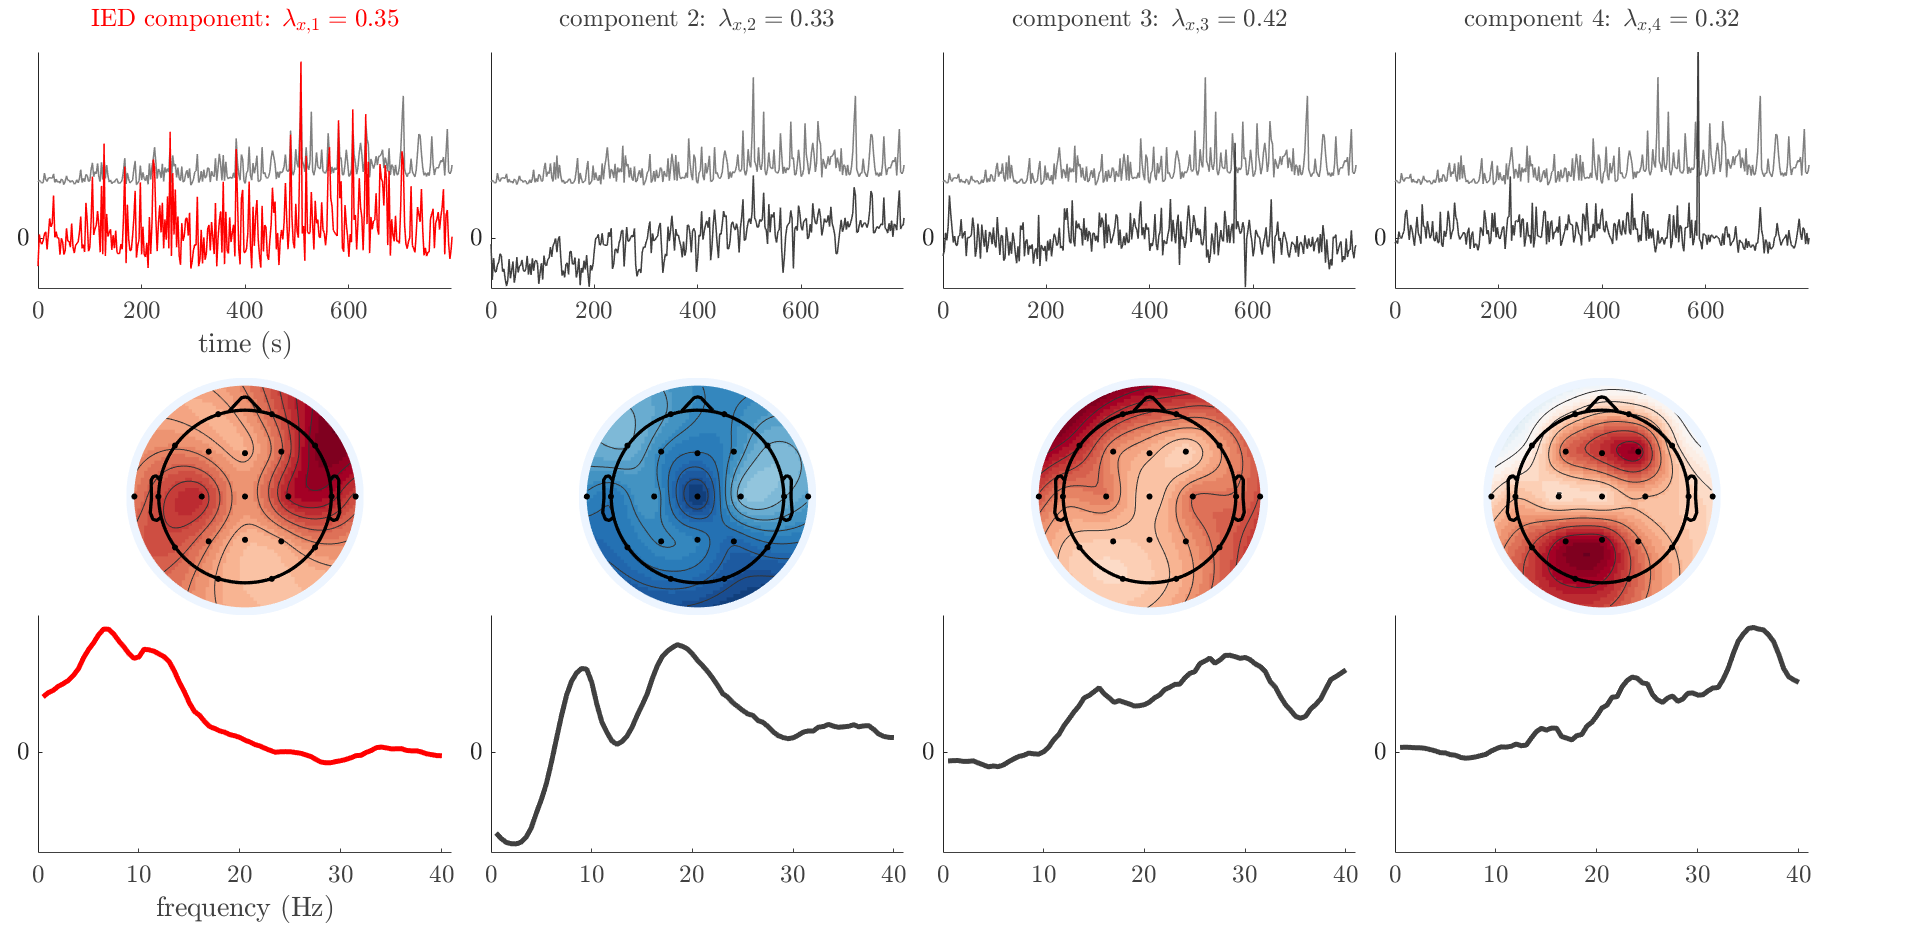

Patient 2

We analyze the solution with sources, and show the results in Figure 3 and 4. As for patient 1, we found a source which is strongly correlated to the MWF envelope, and which had a mostly low-frequency behavior characteristic for spikes. The topography is mostly uninformative, and does not clearly correspond to the patient’s clinical data. The third source is mostly present at both sides of the head, is very sparsely active in time, and has a high-frequency content: this is most likely an artifact due to the neck muscles. Again, there is one of the highest-entropy HRFs which belongs to a ROI in the IOZ. Now, the waveform is clearly resolved from the other HRFs, through the strong initial dip (before 0 seconds). Such a dip is sometimes observed in HRFs, but its underlying physiological mechanism is not yet fully understood. It is possible that this dip reflects altered vascular autoregulation near the IOZ (cfr. the explanation in the Section 1 of the main text), or a rapid depletion in oxygen due to IED generation (before the IED becomes visible on the EEG). Figure 4 furthermore shows that the IED-related component is significantly active in parts of the IOZ, and deactive in others. As mentioned earlier, this deactivation may or may not be due to errors in sign correction. Interestingly, the ROI with the high alteration in neurovascular coupling is distinct from both the activated and deactivated ROIs.